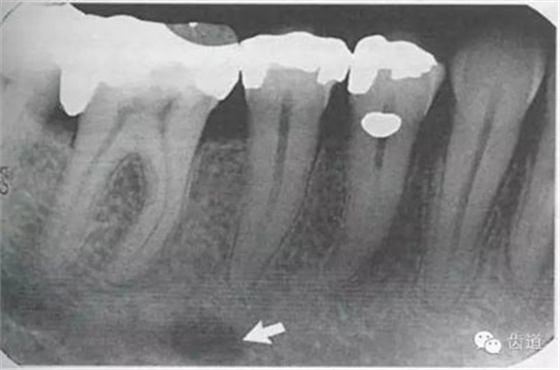

位于前磨牙根尖區(qū)域,為一大致圓形密度低的影像。頦孔位置變異大,多位于第二前磨牙根尖稍下,注意與根尖周病變區(qū)別,其要點(diǎn)是牙周膜及其骨硬板是否連續(xù)不斷。

位于磨牙牙根尖下方,呈寬約為0.4cm凹面向下邊緣整齊的帶狀密度低的影像,其兩側(cè)有密度高的線條狀影像,為下頜管骨密質(zhì)